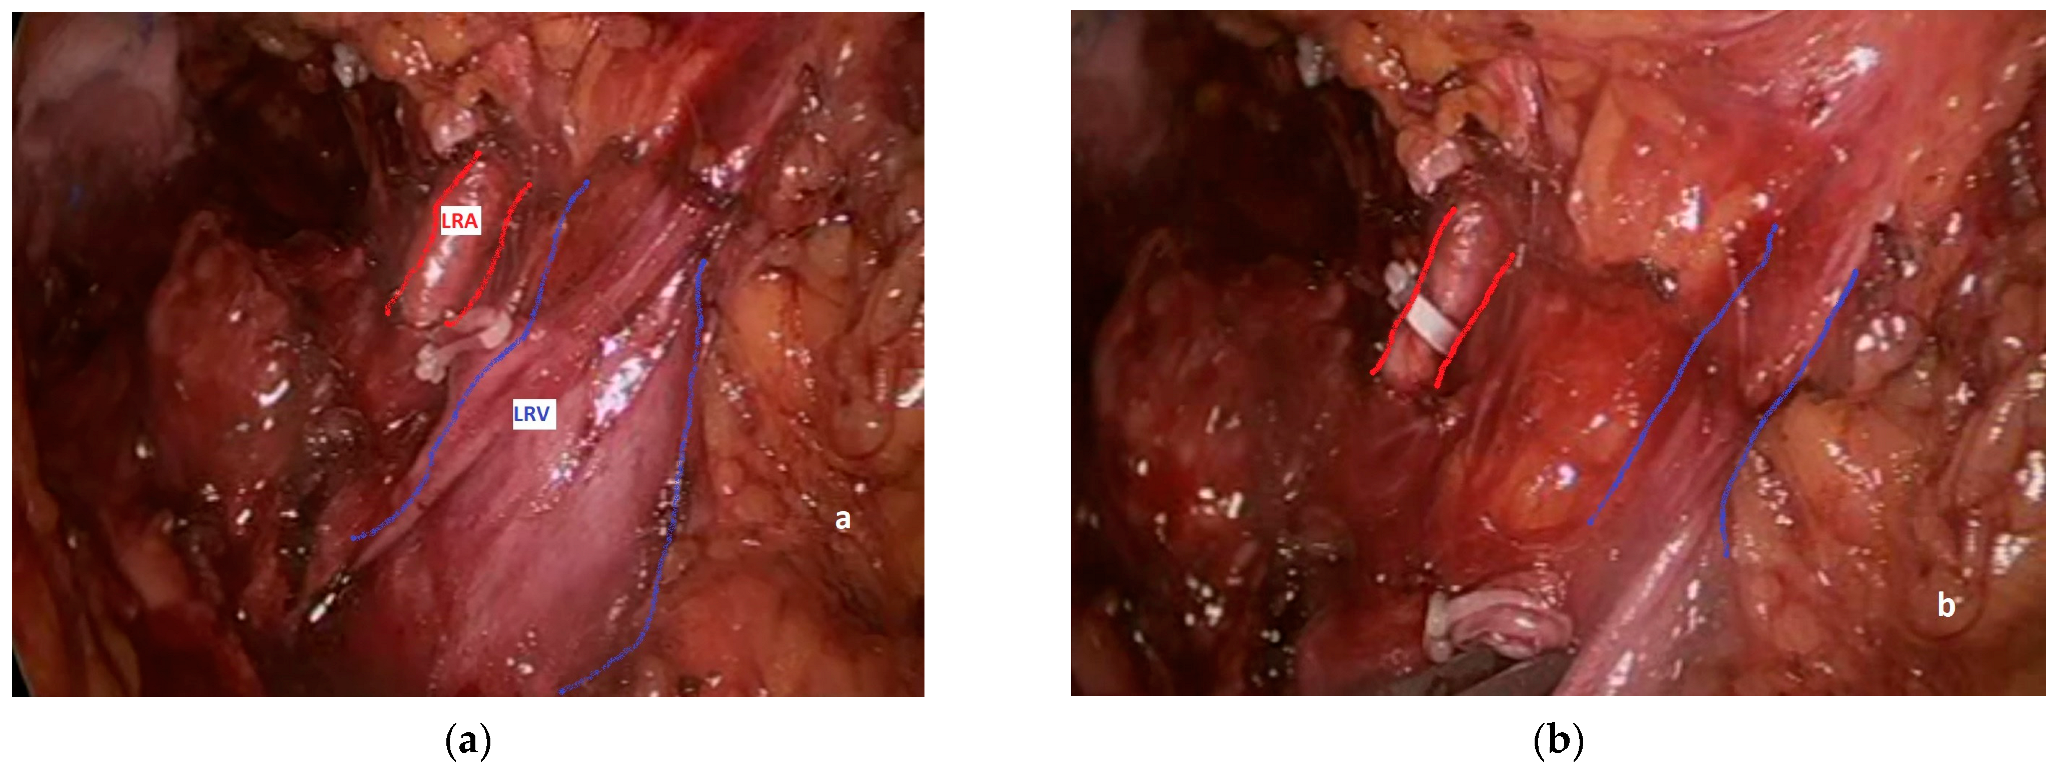

3.3. Pathogenesis, Prevention and Diagnosis

3.4. Clinical Consequences and Treatment